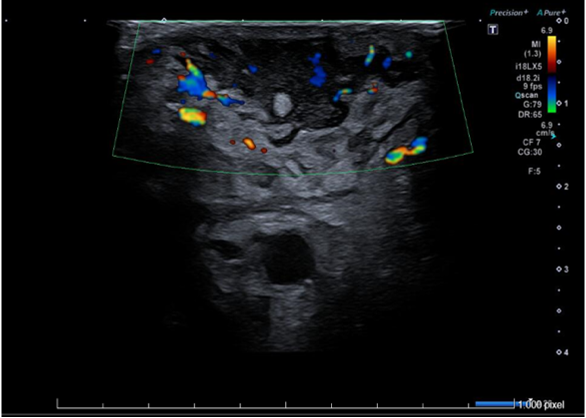

Ecografía de partes blandas de axila izquierda: Piel engrosada con aspecto hipoecogénico y heterogéneo. Tejido celular subcutáneo con cambios inflamatorios y edema, que simula imagen en forma de nubes. Colección de 13x36 mm en tejido celular subcutáneo con márgenes irregulares, contenido ecogénico fluctuante con trazos hiperecogénicos periféricos. Vasos regionales permeables sin signos de trombosis. Hallazgos compatibles con absceso subcutáneo y celulitis.

En el caso de colecciones permite identificar sus características: el tipo de contenido (sólido/líquido), el contorno, la vascularización y la presencia de septos o tabiques. Por otro lado, mejora la toma de decisiones terapéuticas y aumenta la seguridad del drenaje, en caso de ser preciso, al servir de guía durante el procedimiento permitiendo evitar estructuras vasculares y nerviosas.